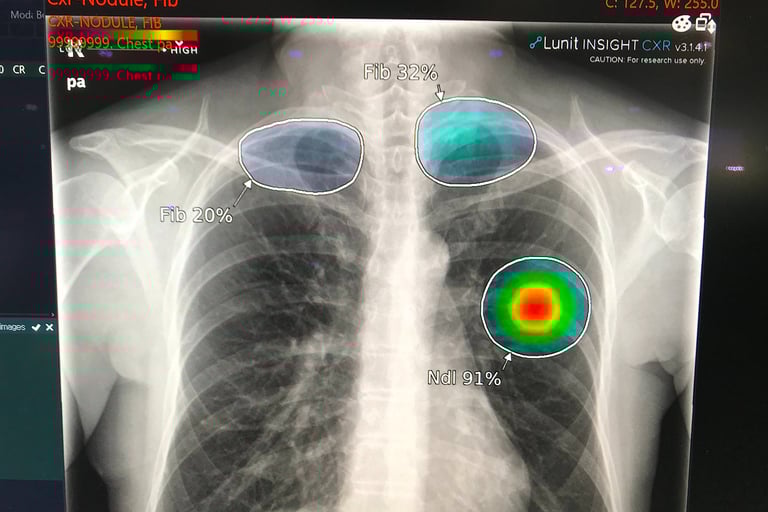

Diagnostic imaging (radiology, pathology)

AI systems can now:

Detect abnormalities faster

Reduce diagnostic error rates

Handle high-volume routine cases